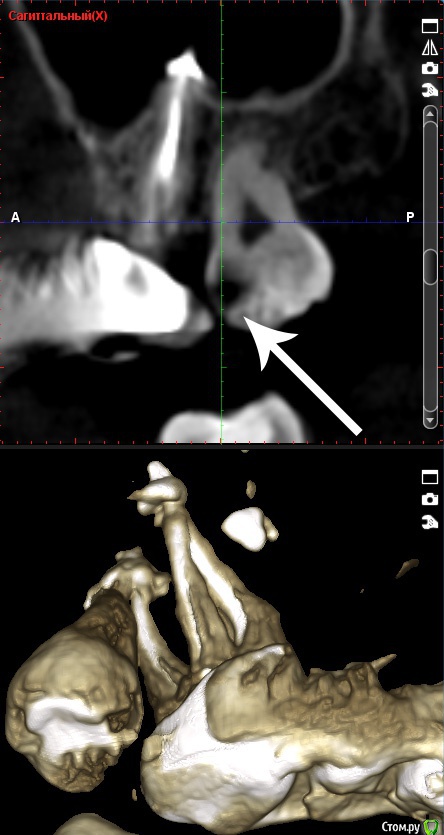

red_butler Опубликовано 20 июня, 2015 Поделиться Опубликовано 20 июня, 2015 Делайте Кт, для начала нужно исключить четвертый корневой канал. Скорее всего понадобится консультация ЛОРа. Узнайте у своего врача, чем пломбировали каналы. Ссылка на комментарий

Natcar Опубликовано 22 июня, 2015 Автор Поделиться Опубликовано 22 июня, 2015 Готово КТ , две ссылки на сайт файлообменника и облако майлруhttp://fayloobmennik.com/iir66p9dhmvl/0011.zip.htmlhttps://cloud.mail.ru/public/3UBG/8CR2mFiZW В клинике где делала снимок возникли вопросы по нижнему зубу -вроде как плохо запломбированный канал. У меня , кстати есть шишка при пульпации щеки на месте этого зуба. Беспокоит и может увеличиваться при простудах. Также слева сверху у семерки увидели незапломбированный канал. Хотя я в мае сходила на лечение в ходе которого мне установили на него коронку. Проблемы с зубом который меня беспокоит сейчас-ничего, кроме того, что много материала выведено за верхушку. В общем, растройстроена. Ссылка на комментарий